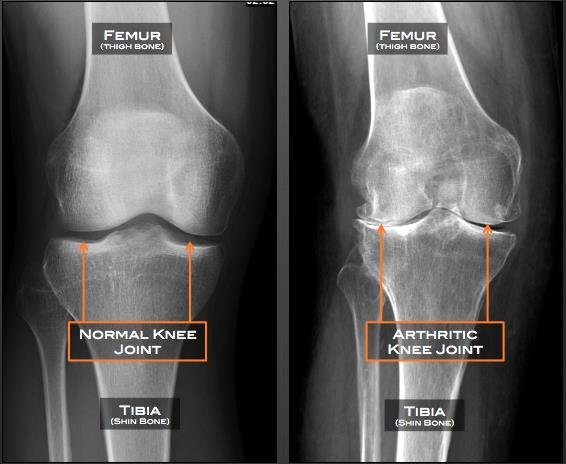

Osteoarthritis of the Knee

Osteoarthritis of the knee happens when cartilage in your knee joint breaks down. When this happens, the bones in your knee joint rub together, causing friction that makes your knees hurt, become stiff or swell. Osteoarthritis in the knee can’t be cured but there are treatments that can relieve symptoms and slow your condition’s progress.